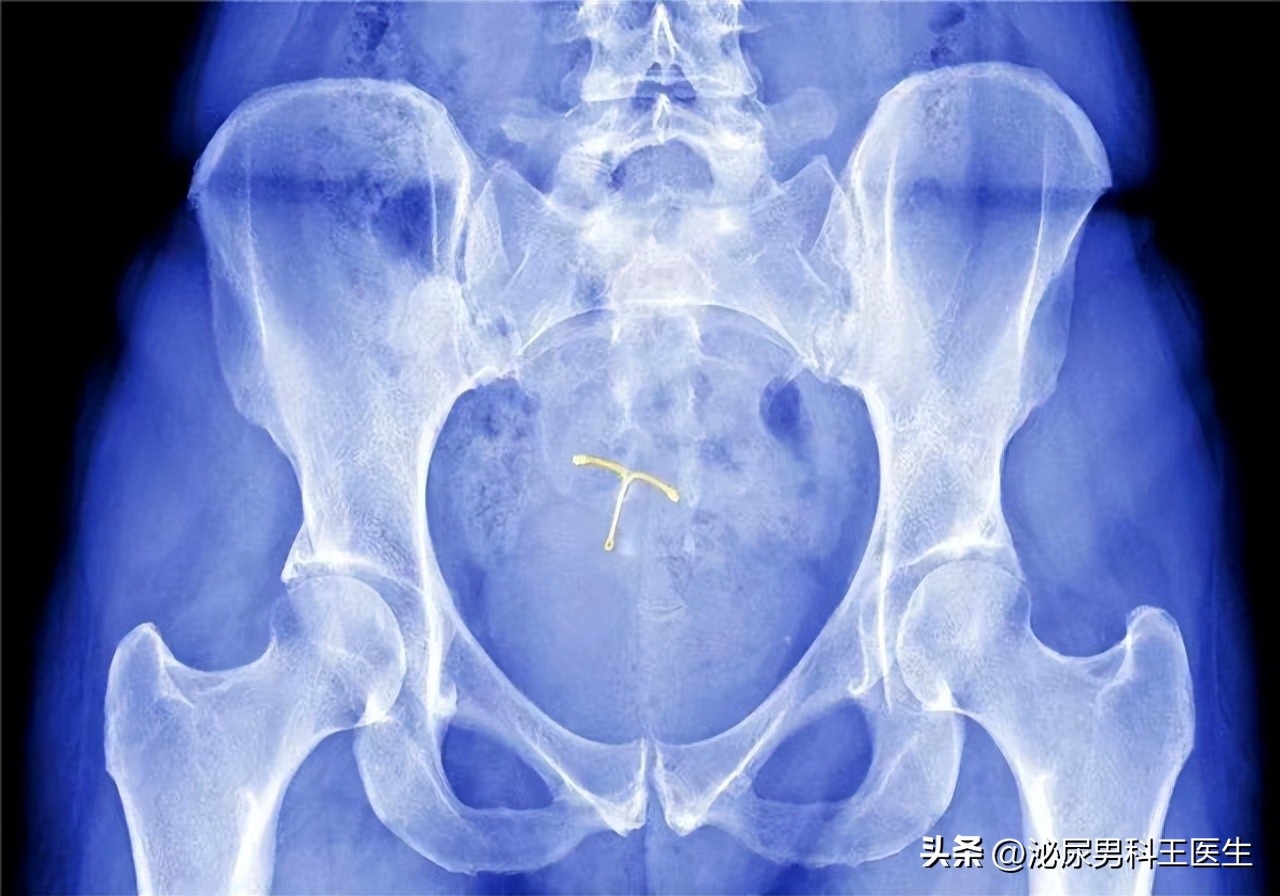

女性放置节育环后出现月经量增多,内分泌失调,或者出现阴道炎症,不明原因阴道流血等现象,可能是由节育环损伤导致的,面对这种情况及时去医院进行x线透视或B超检查,观察节育环在宫颈的情况,确定是由节育环导致的阴道感染等,应尽快进行取环手术。

常见的节育环有铜制宫内节育环,不锈钢丝,塑料,硅胶质,金属单环等等。含药物成分的节育环为活性节育环,不含药物成分的节育环为惰性节育环。

一般节育器可放置5-20年不等 ,具体节育器的使用年限要根据其使用指南而定,超出使用年限可能对女性的危害很大。